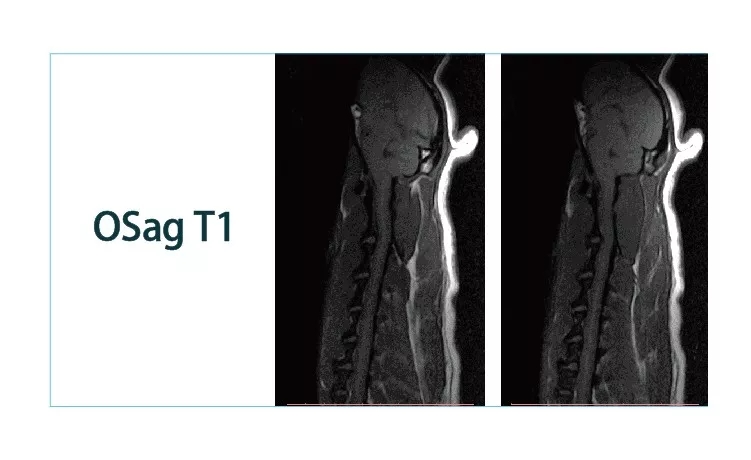

【朗润影像档案】20181221磁共振影像病例结果讨论